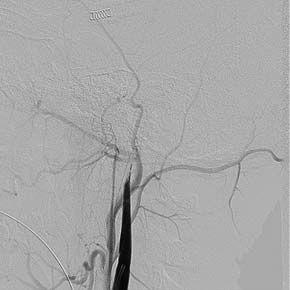

При повторной явке через 4 и 9 мес пациент никаких жалоб не предъявляет. Двигательная активность в конечностях в полном объёме, сенсомоторной афазии нет. Самочувствие хорошее. Уровень активности умеренный (занимается лёгкой атлетикой 3 раза в неделю по 60 мин). При контрольной цереброангиографии патологии не выявлено, контуры стентов ровные, рестенозы и диссекции не визуализируются (рис. 5–7).

Рис. 5, 6. Контрольная цереброангиография через 4 мес. Стенты функционируют нормально